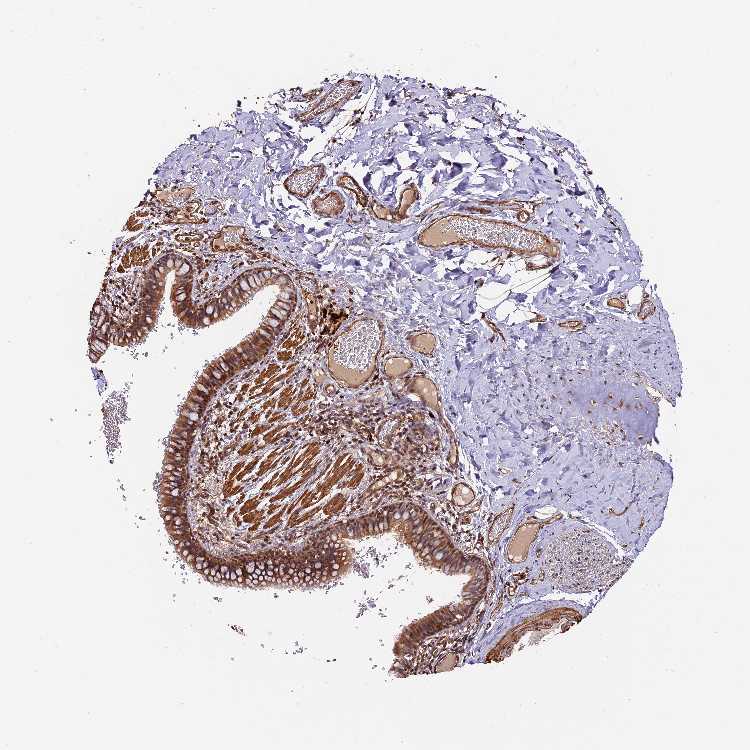

TISSUE PRIMARY DATA BRONCHUS Show tissue menu

Bronchus

BRONCHUS - Expression summary

BRONCHUS - Antibody stainingi

Antibody staining in the annotated cell types in the current human tissue is reported as not detected, low, medium, or high, based on conventional immunohistochemistry profiling in selected tissues. This score is based on the combination of the staining intensity and fraction of stained cells.

Each image is clickable and will lead to virtual microscopy that enables deeper exploration of all samples and also displays staining intensity scores, fraction scores and subcellular localization as well as patient and tissue information for each sample.

Antibody HPA040390Antibody CAB002611

Respiratory epithelial cells HighHigh